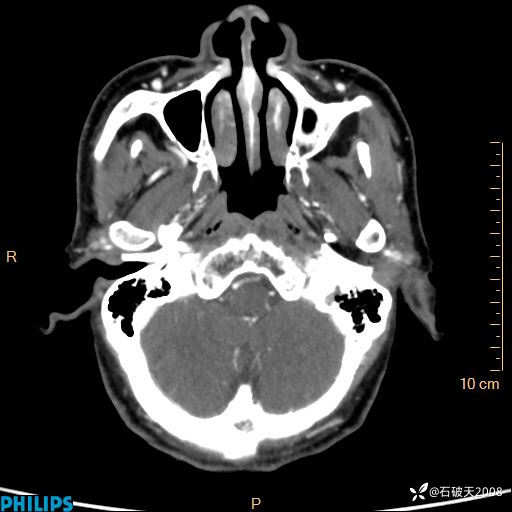

动脉期